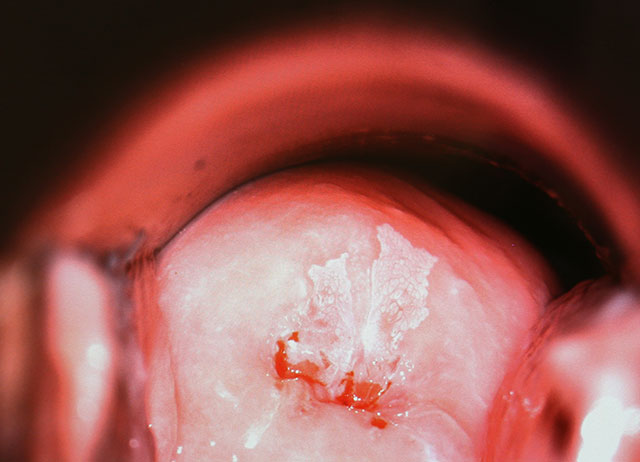

Eine Kolposkopie ist die Betrachtung der weiblichen Genitalien, das heißt der Vulva, der Vagina und des Gebärmutterhalses mit einem Mikroskop. Dies findet im Rahmen einer normalen gynäkologischen Untersuchung statt und ist völlig schmerzlos. Während der Untersuchung wird hochverdünnter Essig auf den Muttermund aufgetragen, damit kann man an Hand verschiedener Zeichen eine schwere Krebsvorstufe mit hoher Sicherheit erkennen. Dieser Untersuchungsschritt kann bei manchen Patientinnen zu einem leichten Brennen führen, welches binnen Minuten wieder verschwindet. Ist der Verdacht auf eine schwere Krebsvorstufe gestellt, wird eine Probe aus dem auffälligen Bereich genommen. Diese Probe ist wenige Millimeter groß und kann genauestens untersucht werden. Normalerweise verspürt man hierbei nur ein kleines Zwicken. Wurde nun eine mittelschwere oder schwere Krebsvorstufe diagnostiziert, erarbeitet der Spezialist in der Dysplasie-Sprechstunde gemeinsam mit dem betreuenden Frauenarzt / der Frauenärztin einen auf die spezielle Situation angepassten Behandlungsplan.